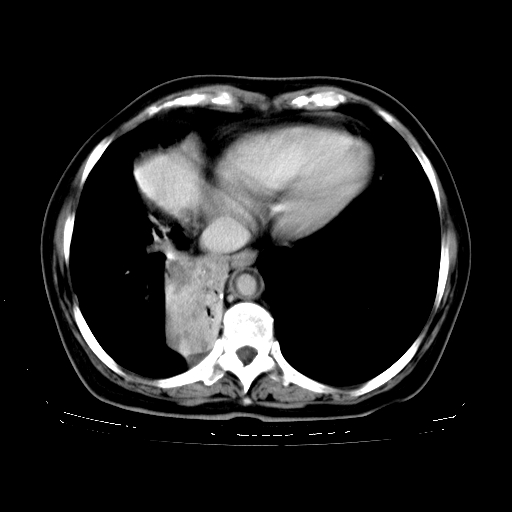

标题: CT23067:女,70岁,咳嗽、咳痰一个月,低热一周。 [打印本页]

女,70岁,咳嗽、咳痰一个月,低热一周。

1.左上肺结核,部分纤维化。右肺中下叶部分肺不张,内见液化、坏死及点状钙化,右中下叶支气管壁增厚、管腔狭窄,见多个点状钙化,结合临床考虑支气管内膜结核,建议痰检查抗酸杆菌并参考血沉。两肺多个小圆点状高密度灶,境界模糊,多考虑结核肺内播散。但本人年龄较大首先应支气管镜检以除外右肺癌。

2.胸主动脉夹层。